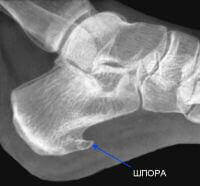

Пяточная шпора — это костный нарост, который появляется на нижней поверхности пятки, в месте крепления подошвенной связки. По сути, это маленький шип или бугорок, который организм создает для защиты травмированного места.

То есть боль в пятках совсем не говорит о том, что у вас шпора, но если затянуть, то она рано или поздно образуется. Точно это можно увидеть только на рентгене.

• Организм запускает защитную реакцию: начинает откладываться кальций — формируется маленький костный нарост (остеофит).

• На рентгене он может быть едва заметен или не виден вовсе.